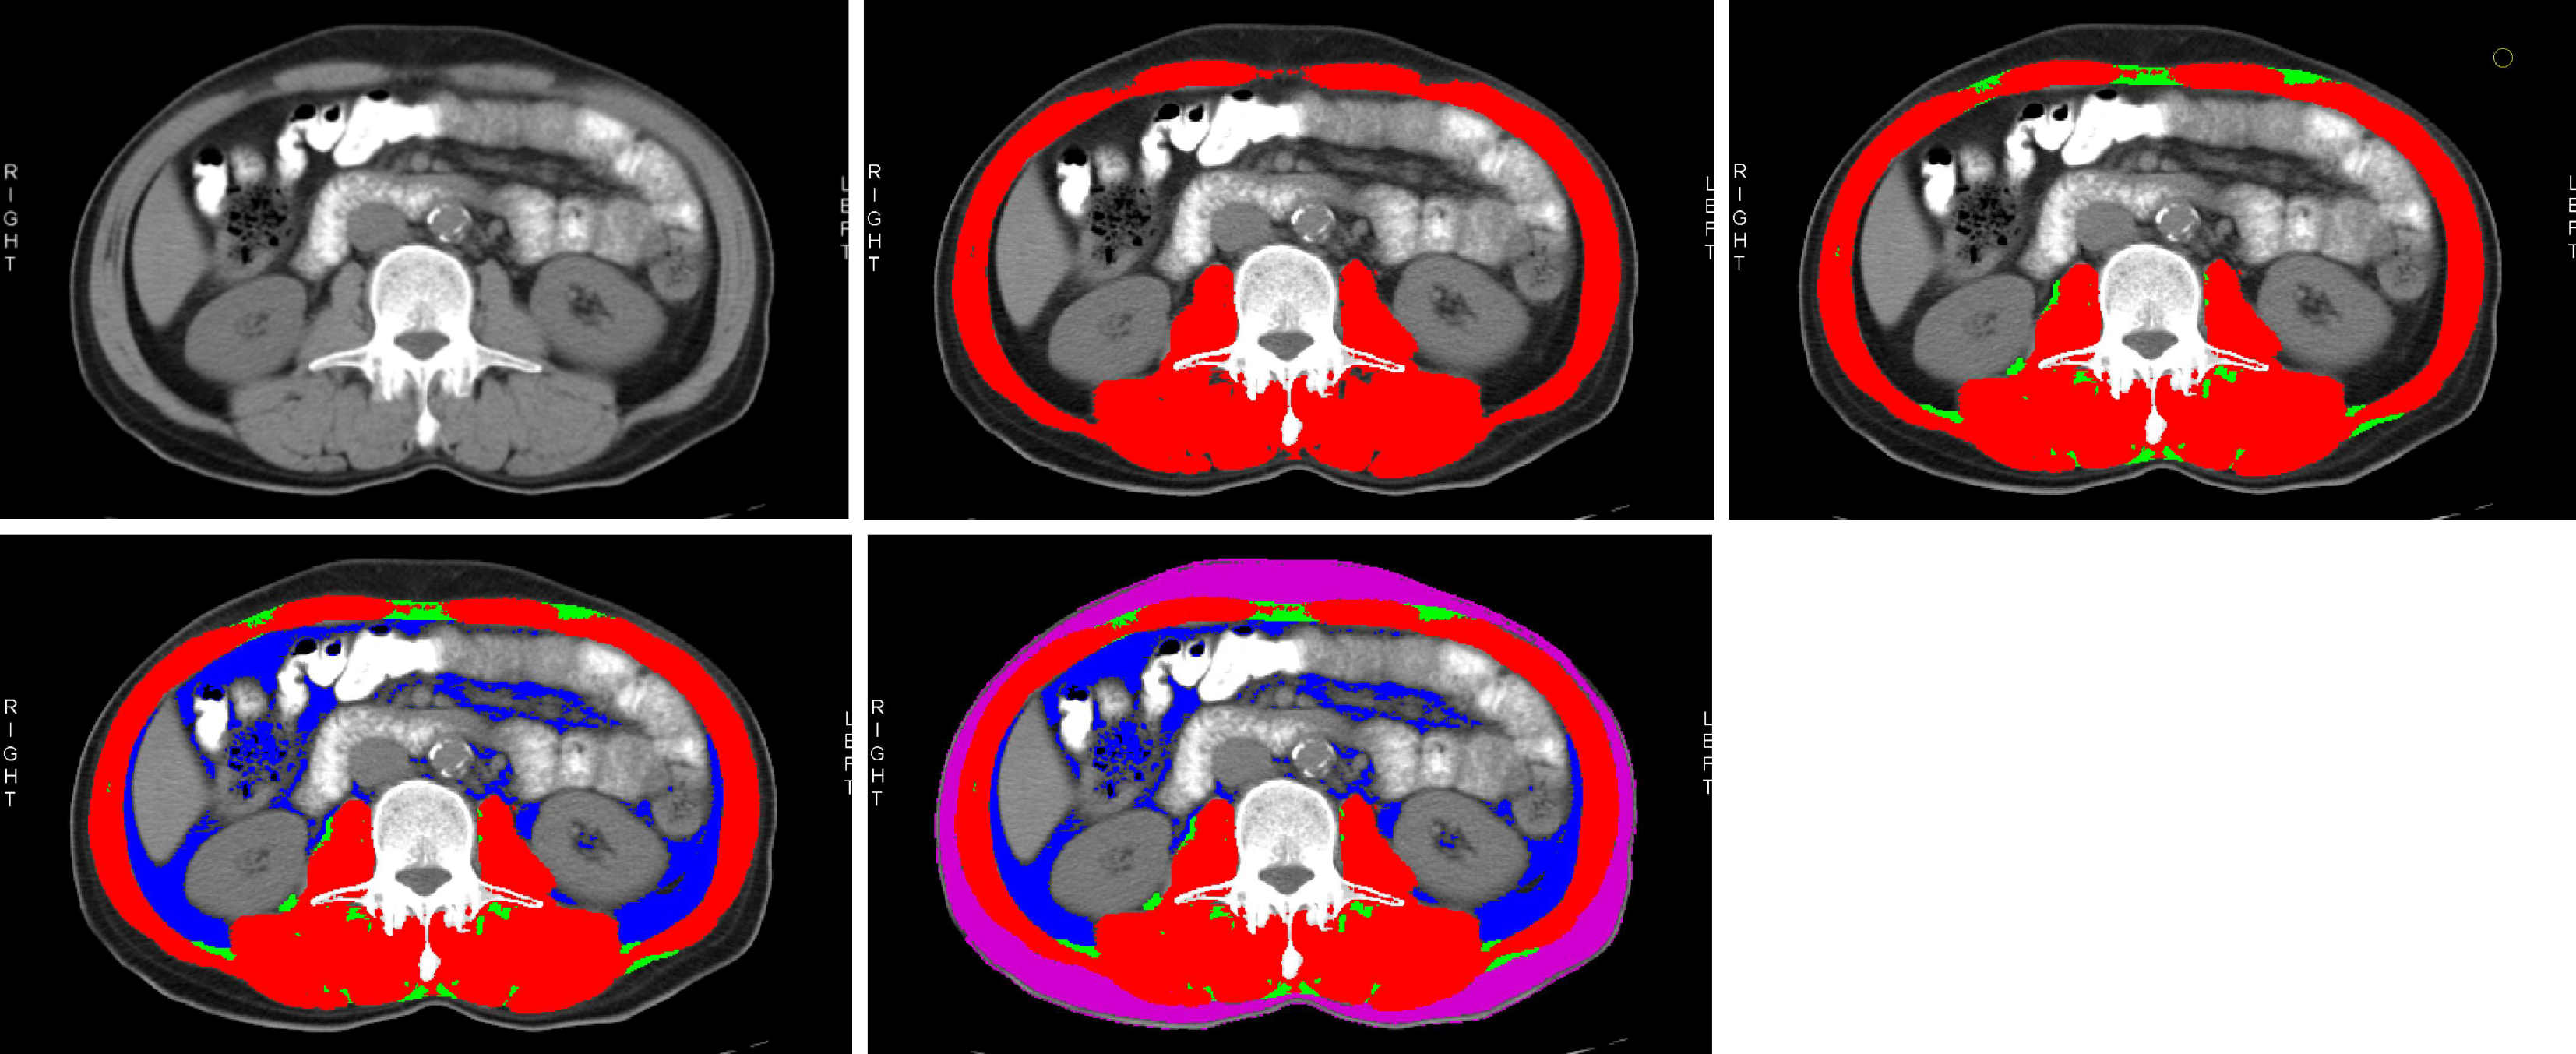

The most recent abdominal CT scans performed before initiating VDZ treatment were selected for each patient. Relevant imaging data were obtained from the radiology department, and images at the third lumbar vertebra (L3) level were chosen for analysis[20]. To verify the reliability of CT-derived body composition measurements, inter-observer consistency was evaluated. Two independent researchers (Xiao-Yan Zhang and Yu-Kun Li), blinded to study design and clinical outcomes, performed image analysis using Slicer O Matic software. Standardized software parameters were applied: Skeletal muscle (-29 HU to +150 HU), SAT (-190 HU to -30 HU), and intermuscular adipose tissue (IMAT; -150 HU to -30 HU). The region of measurement was defined as the cross-sectional area at the L3 vertebra level. Thirty randomly selected CT images underwent duplicate measurements of target parameters (IMAT area, SAT area, and skeletal muscle mass). Inter-observer agreement was quantified using the intra-class correlation coefficient (ICC). ICC values were interpreted as follows: < 0.40 (poor), 0.40-0.59 (fair), 0.60-0.74 (good), and ≥ 0.75 (excellent)[1]. Statistical analyses were performed with SPSS 26.0 software (IBM Corp., Armonk, NY, United States), and a two-sided P value < 0.05 was considered statistically significant (Figure 1).

Figure 1

Figure 1 Representative computed tomography scan at the third lumbar vertebra (L3) level, illustrating regions annotated with Slice-O-Matic software.